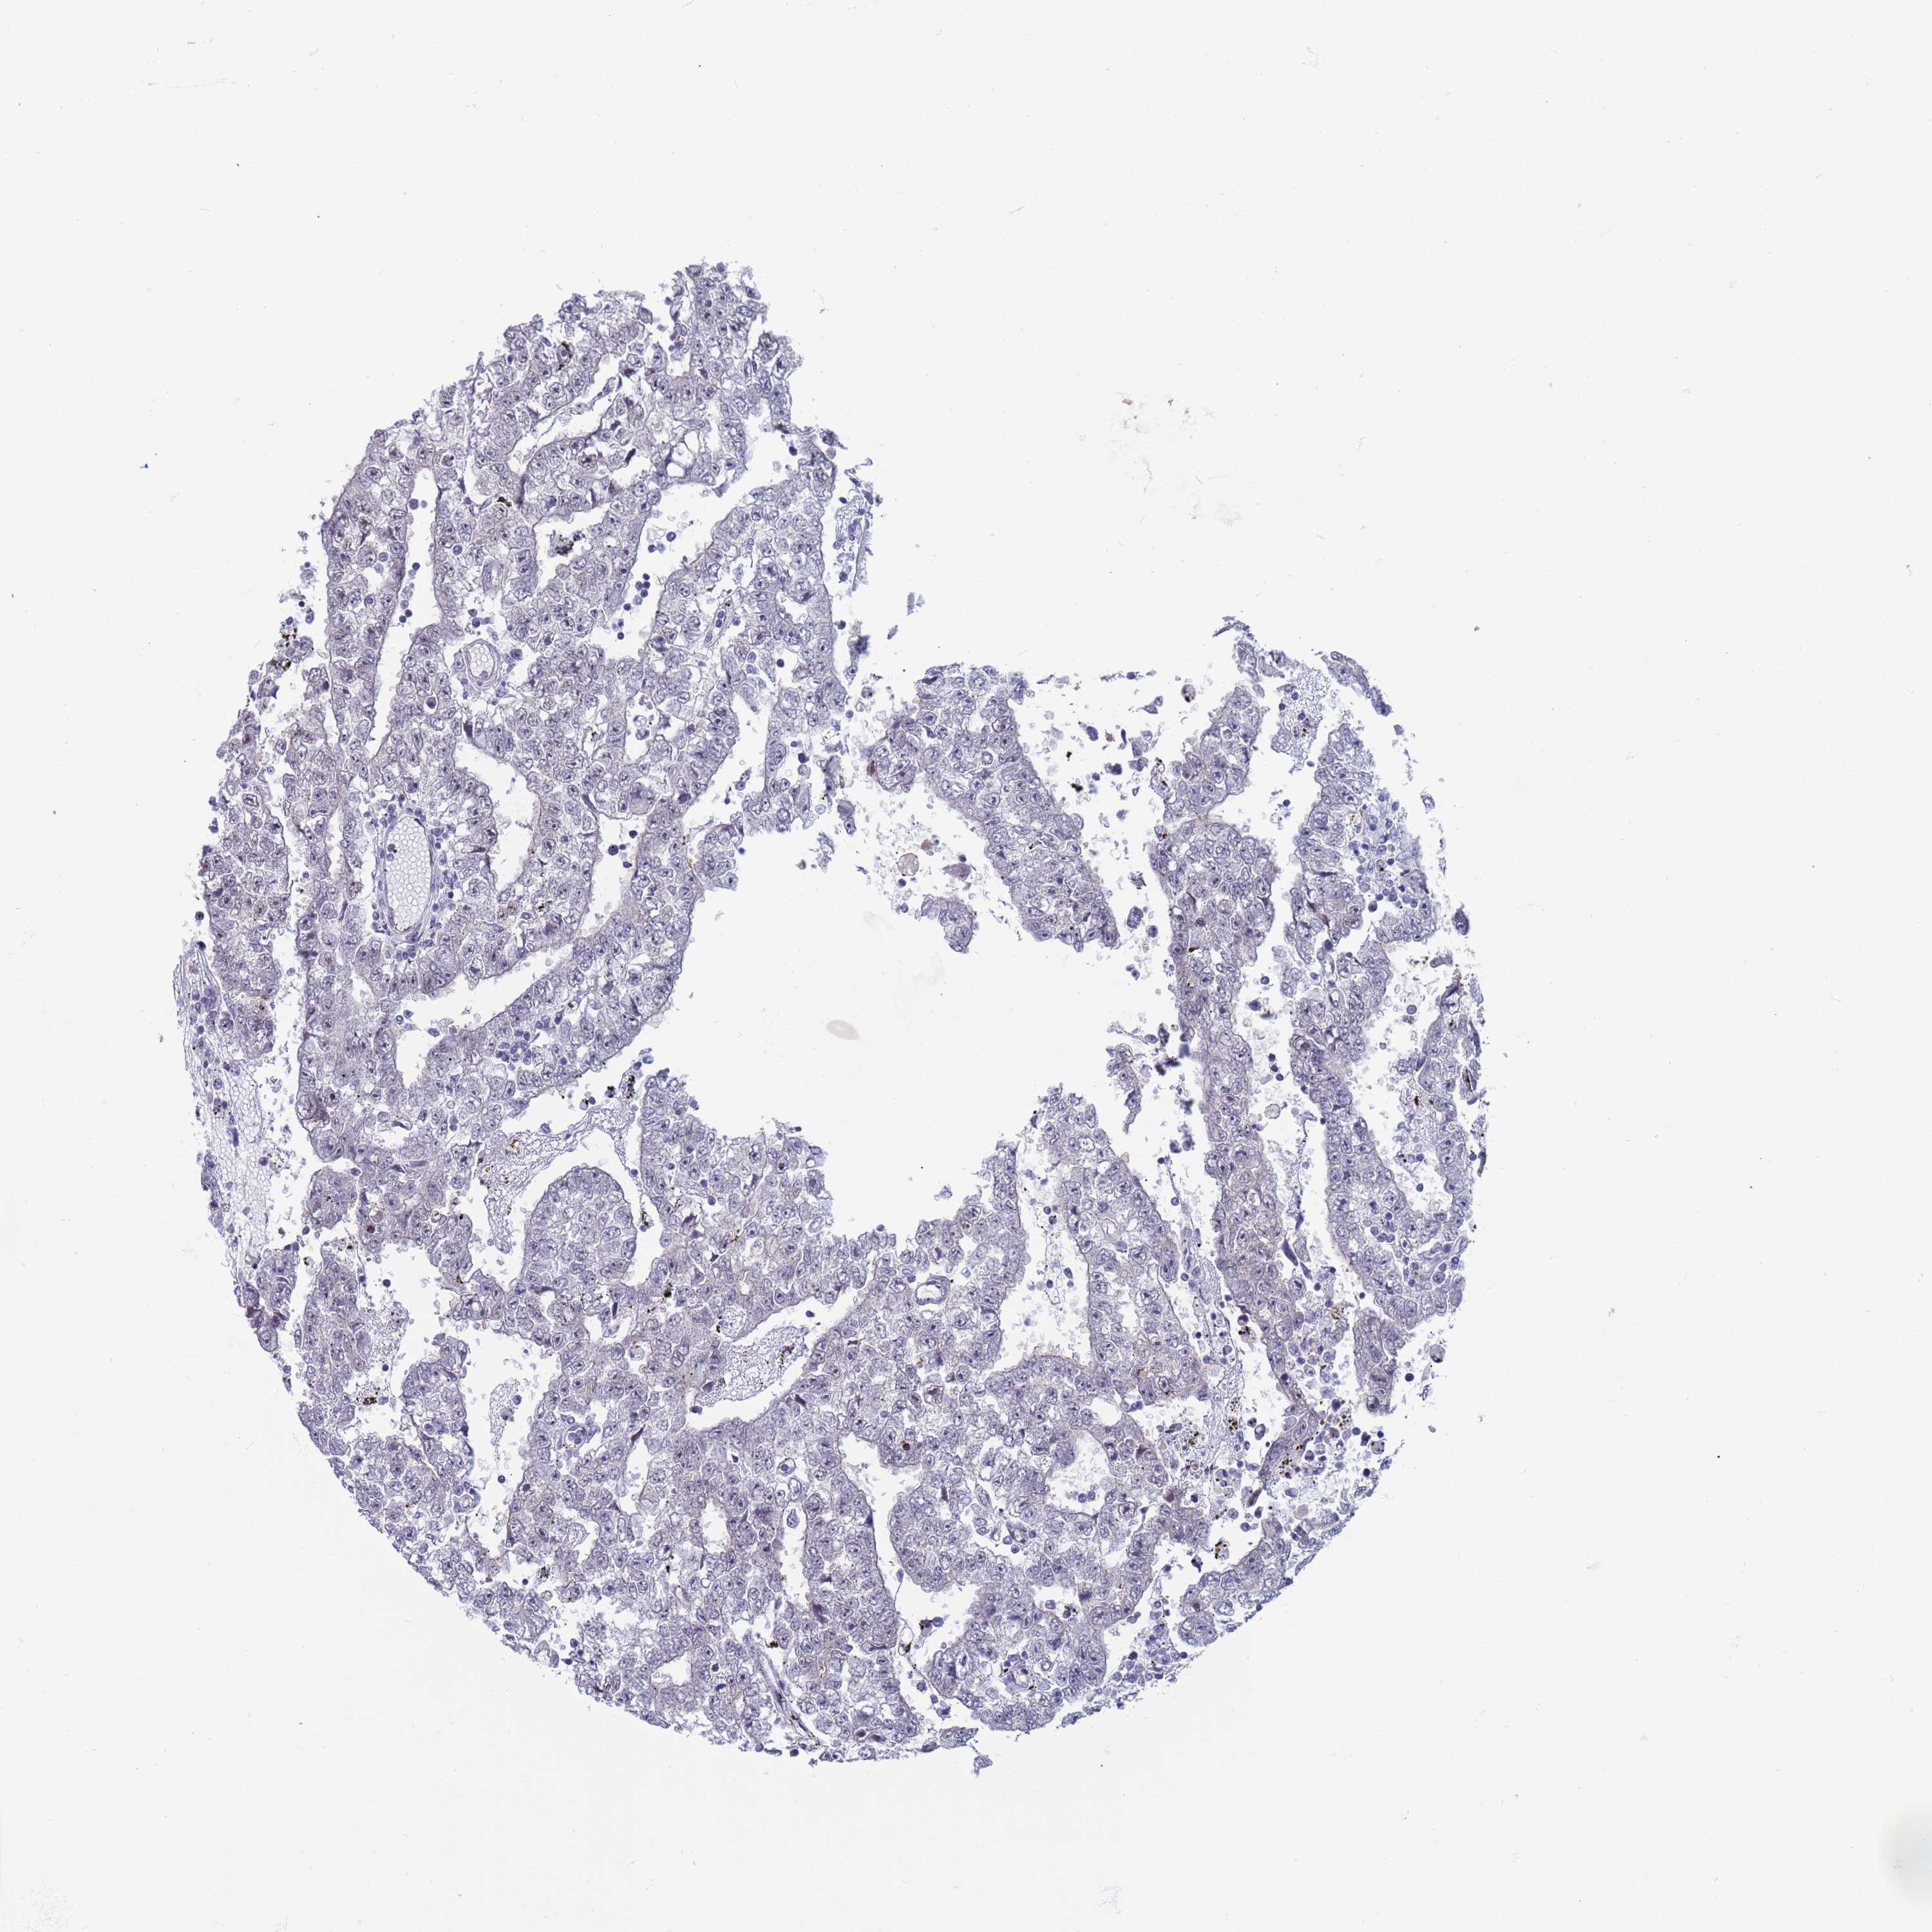

TESTIS CANCER - Protein expressioni

A mouse-over function shows sample information and annotation data. Click on an image to view it in a full screen mode. Samples can be filtered based on level of antibody staining by selecting one or several of the following categories: high, medium, low and not detected. The assay and annotation is described here.

Note that samples used for immunohistochemistry by the Human Protein Atlas do not correspond to samples in the TCGA dataset.

Antibody stainingi

Antibody staining in the annotated cell types in the current human tissue is reported as not detected, low, medium, or high, based on conventional immunohistochemistry profiling in selected tissues. This score is based on the combination of the staining intensity and fraction of stained cells.

Each image is clickable and will lead to virtual microscopy that enables deeper exploration of all samples and also displays staining intensity scores, fraction scores and subcellular localization as well as patient and tissue information for each sample.

Antibody HPA043552

Staining

High

Medium

Low

Not detected

Intensity

Strong

Moderate

Weak

Negative

Quantity

>75%

75%-25%

<25%

None

Location

Nuclear

Cytoplasmic/membranous

Cytoplasmic/membranous,nuclear

Carcinoma, Embryonal, NOS

Seminoma, NOS

Urothelial carcinoma, High grade